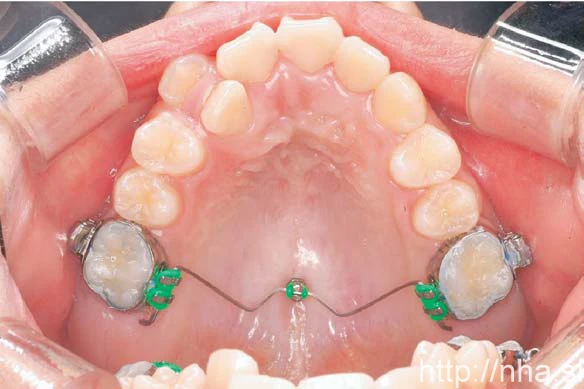

Với điều trị niềng răng mặt trong, minivis có thể được cắm giữa các chân răng ở xương ổ răng phía vòm miệng (Hình 1) hoặc vùng giữa khẩu cái (Hình 2). Ở bệnh nhân là trẻ em, đường khớp giữa khẩu cái vẫn đang mở, trong trường hợp này có thể cắm minivis ở vùng cận giữa khẩu cái (Hình 3). Trong một số trường hợp, có thể cắm minivis ở mặt ngoài ngay cả khi niềng răng mặt trong (Hình 4)

Minivis cắm ở vùng đường giữa khẩu cái

Hình 2 Minivis cắm ở vùng đường giữa khẩu cái.